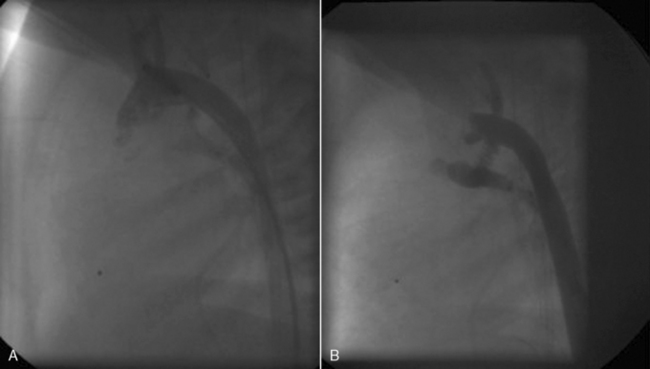

The anomalies addressed here include anomalous coronary artery origins from the pulmonary artery instead of from the aorta; some anomalous aortic origins of coronary arteries; fistulas of a coronary arteries; and congenital atresia of the left main coronary artery.242,446,456,588

Anomalous Coronary Artery Origins from the Pulmonary Artery

Anomalous left coronary artery originating from the pulmonary artery (ALCAPA, Bland White Garland syndrome) is the most common of these anomalies. When the left coronary artery arises from the pulmonary artery, it is likely that no changes occur during fetal life when pressures in the aorta and pulmonary artery are approximately equal. After birth, the left ventricle is perfused with desaturated blood flow from the pulmonary artery, under low pressure; this leads to left ventricular ischemia and often causes heart failure. Soon, collateral vessels develop from branches of the right coronary artery to branches of the anomalous left coronary artery. Once the collateral vessels develop, blood flow from the right coronary artery travels retrograde through the branches of the left coronary artery into the low resistance pulmonary artery, instead of perfusing the high resistance coronary vasculature. The effect is a “steal” of right coronary blood flow, causing angina and ischemia.242

Anomalous Coronary Artery Origin from the Pulmonary Artery

Diagnosis of anomalous left coronary artery originating from the pulmonary artery (ALCAPA) is an indication for surgery. A median sternotomy incision, cardiopulmonary bypass, hypothermia, and cardioplegia are typically used for this surgery. Careful management is necessary in patients with symptoms of poor myocardial perfusion, to avoid ventricular fibrillation before establishing cardiopulmonary bypass.

Surgical strategies are aimed at constructing a system of two coronary arteries perfused with aortic blood flow. Surgical approaches vary depending on the position of the coronary artery in relation to the aorta. If possible the left coronary artery is transferred from the pulmonary artery to the aorta. A Takeuchi procedure (tunnel repair) may be required if the coronary artery is not near the aorta. An aortopulmonary connection (window) is created and blood from the aorta is tunneled through the window to the coronary origin in the pulmonary trunk.

In older patients when other alternatives are not possible, a connection from a subclavian artery to the coronary artery (Meyer procedure) may be created to provide coronary arterial flow. Coronary bypass grafting techniques may be used in some cases. Another option is ligation of the coronary artery to eliminate the steal phenomenon, but this is associated with higher mortality.

Death in the first year of life occurs in about 65% of patients with ALCAPA if there is no surgery. Surgical intervention is associated with high early and late survival, especially if there is no significant left ventricular dysfunction or mitral regurgitation preoperatively.154,497,588

When the right or both coronary arteries originate from the pulmonary artery the surgical approach is similar to that described above.497 ARCAPA has a lower surgical risk than ALCAPA.947